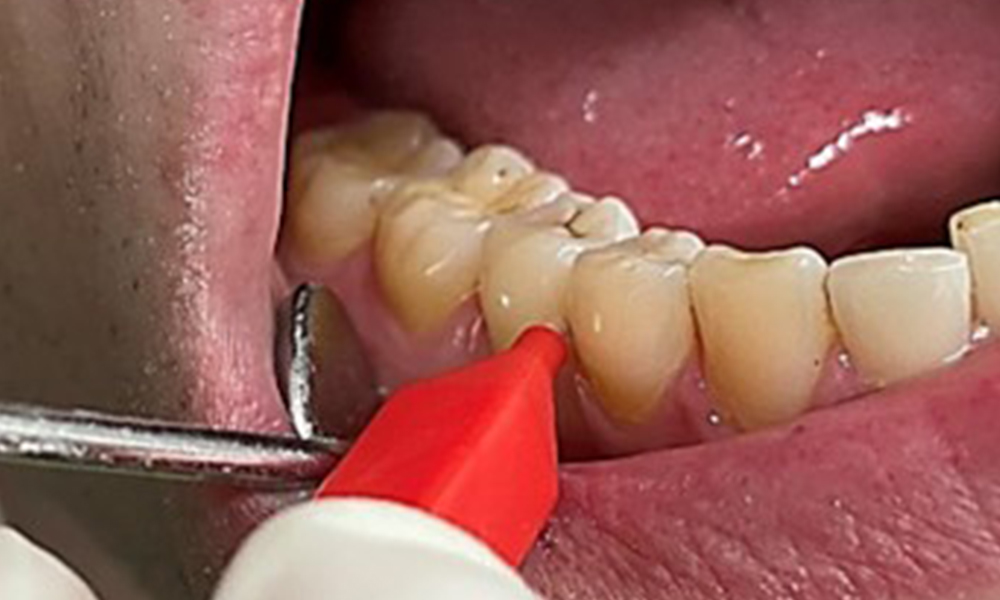

Lors de l'utilisation de poudre plus abrasive, il est essentiel de travailler d'une direction cervicale à une direction coronale et de ne jamais diriger la buse de sortie vers la gencive afin d'éviter un emphysème potentiel. Une bonne aspiration du côté controlatéral est essentielle pour réduire la formation d'aérosols (Fig. 12).